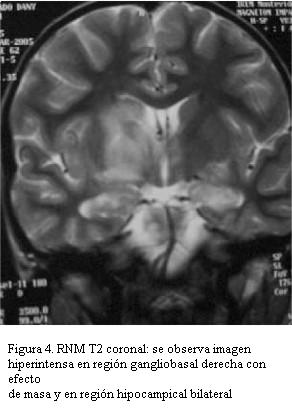

RNM: extensas lesiones hiperintensas en T2 y Flair gangliobasal externo e interno derecho incluyendo cápsula interna con ligero efecto de masa. Lesión de tálamo a izquierda y lóbulos temporales a nivel de los uncus del hipocampo bilateral y cerebelo. Lesiones a nivel de ambos pedúnculos cerebrales, protuberancia y sector anterior de bulbo. Angiorresonancia: gruesos troncos arteriales de territorio cerebral anterior, media y posterior permeables, menor visualización de ramas arteriales secundarias que aparecen adelgazadas (figuras 3 y 4).

La resonancia magnética nuclear es el examen de elección para confirmar estas alteraciones, revelando en el neuro-Behçet tres patrones característicos: una fase inicial en la que se evidencian focos de hiperintensidad en T2 a nivel de tronco cerebral, gangliobasal y hemisferios cerebrales; una fase intermedia con mayor inflamación que causaría edema y efecto de masa que puede regresar espontáneamente o con tratamiento inmunosupresor, pudiendo encontrar focos de microhemorragia con hiposeñal por los depósitos de hemosiderina, y finalmente en la fase crónica predominan imágenes de atrofia especialmente en tronco encefálico. El seguimiento neuroimagenológico evidencia regresión o desaparición de las lesiones parenquimatosas a largo plazo (meses a años) (19).